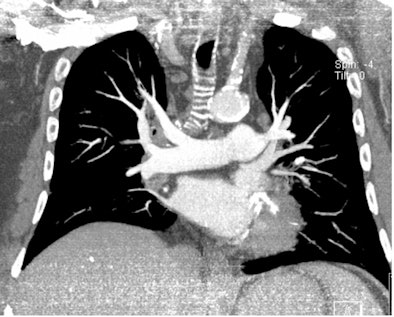

| All three CT images are from the same female patient weighing 95 kg with no pulmonary emboli. Above are two coronal maximum intensity projection (MIP) images, and below is a 1-mm thin transverse slice. At this body weight, 80-kVp CT angiography protocols provided good image quality and a high enough diagnostic confidence to exclude pulmonary embolism. All images courtesy of Dr. Zsolt Szücs-Farkas. |

A cohort comprising 100 patients with suspected pulmonary embolism (no other exclusion criteria) underwent CT angiography (Somatom Sensation 16, Siemens Healthcare) at 80 kVp, using real-time automatic mAs-modulation (CareDose 4D) and a reference mAs of 150, following an injection of 75 mL contrast medium at 3 mL/sec. The patients were divided into six groups by weight.

Szücs-Farkas concluded that "80 kVp gives sufficient diagnostic image quality at low exposure in patients weighing up to 100 kg."

There were no significant differences measured in image noise between patient groups above 50 kg and contrast-to-noise ratio in the 71-80 kg, 81-90 kg, and 91-100 kg groups. There also were no significant differences between all patient groups in the subjective ranking of enhancement, detectable ramification of the pulmonary arteries, subjective grading of noise in the vessels and mediastinum, or overall image quality.

The mean attenuation of the pulmonary arteries exceeded 300 HU in all body weight groups.